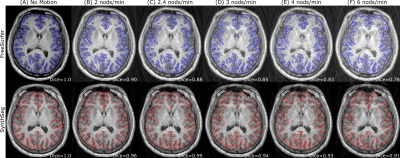

Figure 2. Example MPRAGE from the GNC dataset (A) augmented with simulated motion artifacts at a nodding frequency of 2/2.4/3/4/6 nods/min (B/C/D/E/F) and resulting cortical segmentations using either FreeSurfer (top row) or SynthSeg (bottom row). The Dice coefficient of the segmentations in (B)-(F) in relation to the segmentation in (A) was 0.90/0.88/0.85/0.83/0.78 for FreeSurfer and 0.96/0.95/0.94/0.93/0.91 for SynthSeg.